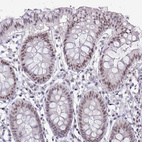

Immunohistochemical staining of human colon, kidney, liver and testis using Anti-RBL1 antibody HPA056525 (A) shows similar protein distribution across tissues to independent antibody HPA054962 (B).